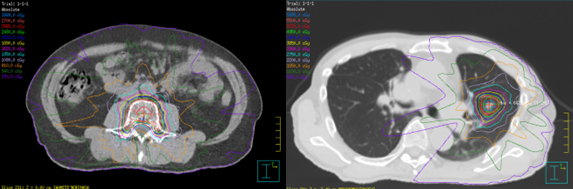

2)定位放射線治療(SRT)

限局した病変に対して高精度に集中照射を行う治療です。当院では手術適応のない(もしくは手術を希望されない)早期の肺がん、他臓器がんからの肺転移、脊椎転移、オリゴ転移病変(数や部位が限られた転移)などを対象に治療を行っています。